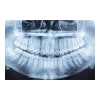

A deep-learning model analyzed CT images to reveal the spatial relationships between key anatomical landmarks of craniomaxillofacial bones. Image courtesy of Torodagli et al.The study authors also highlighted that the model showed good generalizability. They suggested that the results were due to the RRN's ability to learn the functional relationships between craniomaxillofacial landmarks that are still present to some degree in cases of large deformities.